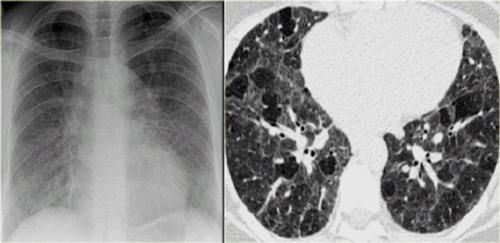

Bệnh nhân ở giai đoạn I.

Có hạch to rốn phổi và cạnh khí quản, không có dấu hiệu tổn thương nhu mô phổi.

Sarcoidosis: hình ảnh điển hình với các nốt dọc theo bó mạch phế quản và các khe liên thùy. Lưu ý hạch vôi hóa một phần ở rốn phổi trái.